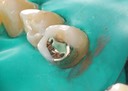

Joe Cha #20 prep